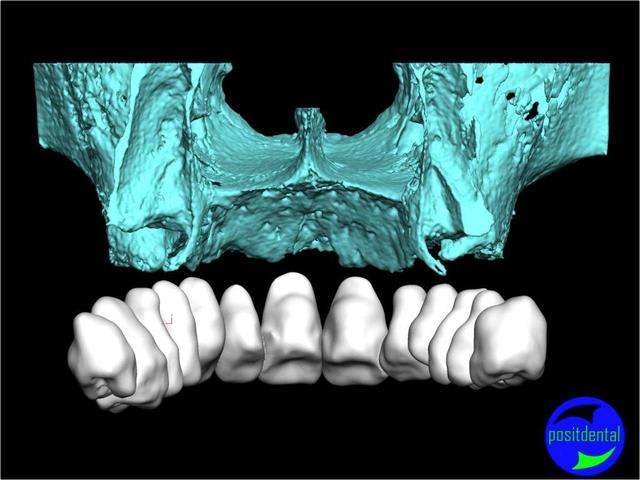

Posit fait une étude pour démontrer la faisabilité de son système, et honnêtement sa démarche semble intéressante, et provoque une réflexion sympa chez D57 et moi même.

La solution unique n'existant pas il est très intéressante que nous échangions nos différents points de vue.

La solution sera une expansion, (what else?) mais dirigée du point de vue prothésiste pour la partie mécanique, ce qui devrait être plus sécurisant pour le patient, et constructif pour nous tous.

une autre vue du photshopman:

modèle stéréo du à la gentillesse de Posit